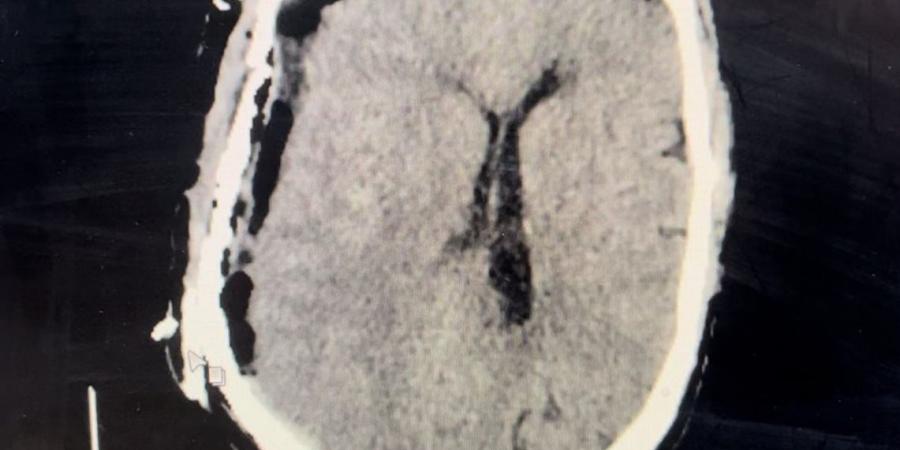

وأوضح أن الحالة كانت حرجة للغاية عند الوصول، حيث أظهرت الفحوصات وجود نزيف حاد أسفل الأم الجافية، ما استدعى التدخل الجراحي الفوري دون تأخير.

وأشار إلى أنه تم إجراء جراحة دقيقة لتفريغ النزيف والتحكم في الشريان النازف، مع متابعة الحالة بشكل مكثف داخل العمليات، مؤكدًا أن سرعة اتخاذ القرار والتدخل في الوقت المناسب كان لهما الدور الأكبر في إنقاذ حياة المريض وتحسن حالته بشكل كامل.